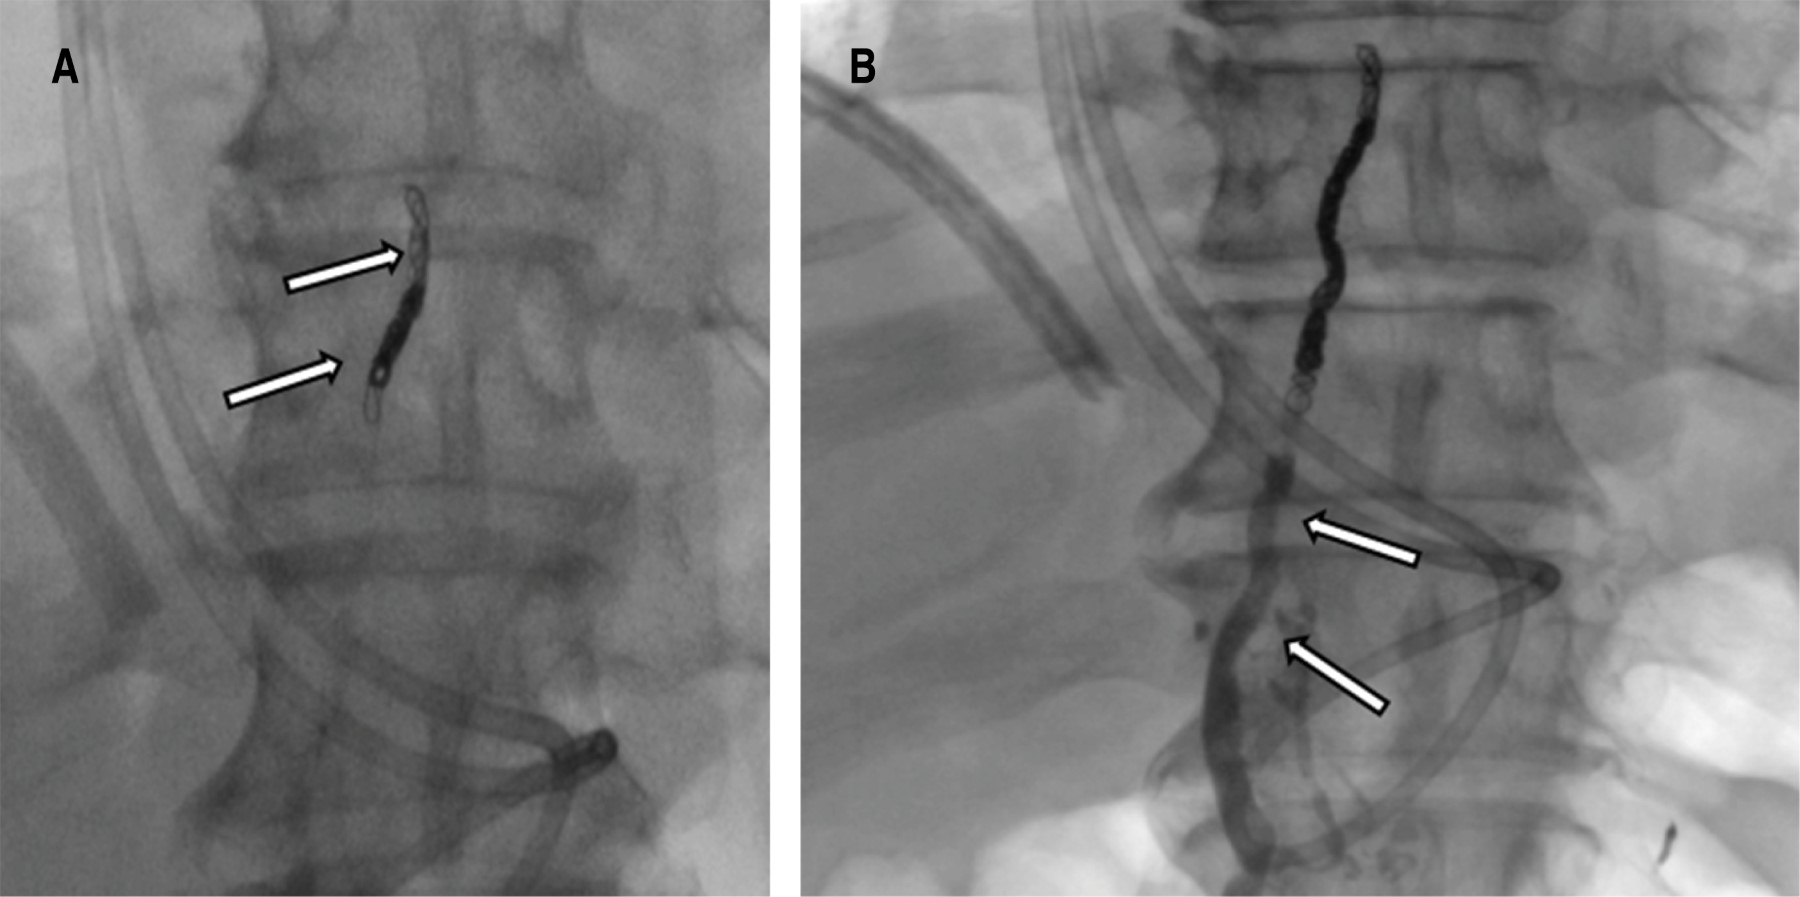

Embolización del conducto torácico

Una vez opacificada la cisterna del quilo, se visualizó una disrupción del conducto torácico y fuga del contraste hacia la cavidad pleural izquierda, bajo control fluroscópico se procede a cateterizar el conducto torácico utilizando una aguja Chiba de 22G por abordaje percutáneo abdominal en la zona epigástrica y con una angulación ligeramente craneal. Una vez que se accede, se introduce una guía de 0.014 pulgadas en el conducto torácico y se cambia la aguja por un microcatéter, el microcatéter se coloca lo más cerca posible al sitio de la lesión del conducto torácico, lo ideal es unir el punto de extravasación (Figura 2). Posteriormente se embolizó con microcoils de 2 y 3 mm de diámetro proximal a la fuga y se completó la embolización con cianoacrilato. En la ductografía de control se objetivó la resolución de la fuga (Figura 3).